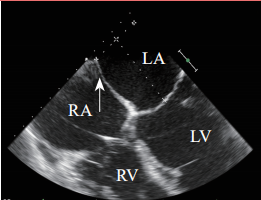

超声心动图在MR介入术中起着不可或缺的作用,下面以目前最为成熟的经导管二尖瓣夹合术MitralClip为例,阐述MR介入术中的超声评价。MitralClip是在经食管超声心动图实时监测和引导下的操作,所有的导管操作由经食管超声心动图监测和引导[17]。经食超声心动图首先引导房间隔穿刺,使得房间隔穿刺点距二尖瓣瓣环平面的高度为3.5~4.0 cm(图12)。之后,经食管超声心动图引导输送系统进入左心房并调弯、顶端垂直指向二尖瓣口。接着,经食管超声心动图引导夹合器在二尖瓣上方定位、夹合器进入左心室、引导夹合器捕获和夹合瓣膜。夹合器捕获瓣膜位置,应该位于彩色多普勒显示反流束最大处。在整个手术过程中,两个超声视野非常重要,为手术的工作切面,其中X-plane双切面,包括三腔心切面(左心室长轴切面)及二尖瓣交界处二腔心切面(图13)。三腔心切面可以显示二尖瓣A2、P2的位置,捕获瓣膜前二尖瓣夹合器应该在这个切面显示为V字形,此时瓣夹合器臂与二尖瓣开放线垂直,分别位于A2、P2的位置,在该切面通过调整夹合器位置可使得夹合器更靠近前叶或后叶;二尖瓣交界处二腔心切面显示P1、A2、P3,捕获瓣膜前二尖瓣夹合器在该平面应该为直线形,在该切面通过调整夹合器位置可使得夹合器更靠近瓣环内交界(P3或A3)或外交界(P1或A1)。另外一个工作切面为三维超声心动图的“二尖瓣外科视野”,可以整体观察夹合器的位置、臂指向的方向(图14)。目前有限经验显示,经心尖二尖瓣夹合术(ValveClamp)术中超声心动图指导和MitralClip总体上类似,但仍有部分差异,其超声心动图规范尚在探索中。

注:LA,左心房;LV,左心室;RA,右心房;RV,右心室

图 12 经食管超声心动图食管中段的四腔心切面,显示房间隔穿刺平面距二尖瓣瓣环平面的高度(箭头所示)